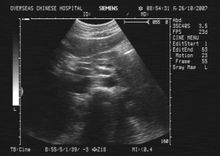

B超BUS检查

B超BUS检查具有无创、安全、快速、廉价及重复性好的特点,常作为首检查方法,并具有筛选价值,B超是诊断的首选方法。主要图像特征有以下几点: (1)多数患者有

胆囊结石,结石位于胆囊或胆囊颈部,胆囊壁增厚,胆囊可见扩张、萎缩或胆囊大小正常。

(2)

胆囊管开口上方的肝总管、肝内胆管扩张或不扩张。

(3)胆总管直径大小正常。

Joseph描述胆总管直径正常,可见到扩张的

胆囊管、肝总管及

门静脉,即所谓的“三管征”(triplechannelsign)。 见到“三管征”应考虑为硬化性

胆管炎,但是临床上很少见到“三管征”。何效东等报道32例中23例行B超检查,仅有2例出现“三管征”。肝总管狭窄及

胆囊胆管瘘患者,由于患者的

胆囊萎缩,显像不佳,再加之胆总管显示不清,较难判断。Ⅰ型嵌顿

结石均容易显示。文献认为凡是临床有反复发作的

胆管炎、梗阻性

黄疸而超声显示胆囊颈或

胆囊管结石,胆囊壁增厚的患者,特别是BUS诊断同时发现肝总管及

肝内胆管扩张而胆总管不扩张者应高度怀疑本病的可能。